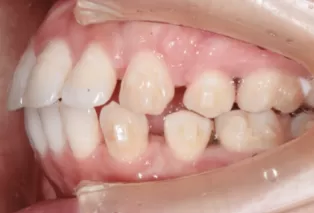

Intraoral photos